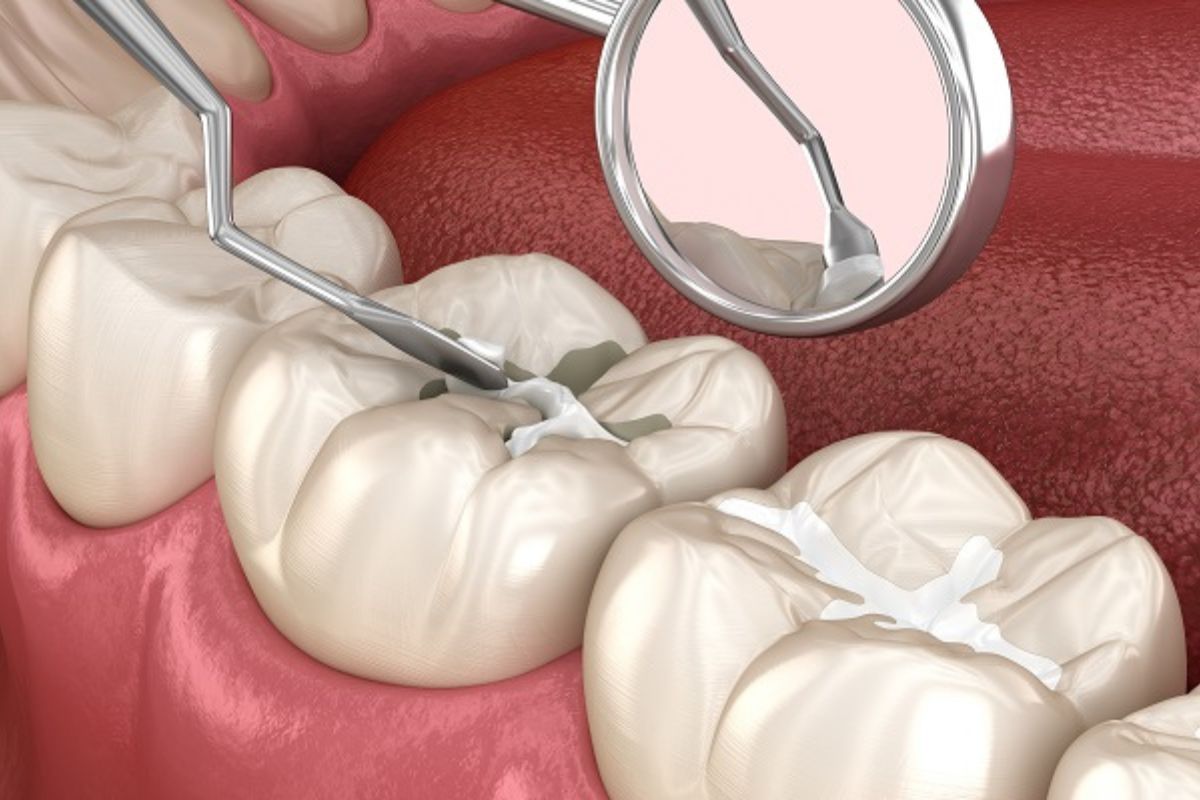

Dental sealants are thin, protective coatings made of plastic or other dental materials that are applied to the chewing surfaces of your back teeth (molars and premolars). These teeth have grooves and pits where food particles and plaque can accumulate, making them more susceptible to cavities.

The sealant creates a smooth surface, filling in these grooves and acting as a shield against harmful bacteria and acids that cause tooth decay.

Sealants work by creating a barrier between your tooth enamel and cavity-causing bacteria. Here’s how the process typically goes:

- Cleaning the Teeth: The dentist thoroughly cleans the teeth to ensure no plaque or debris is trapped beneath the sealant.

- Preparing the Surface: A special gel is applied to the tooth to roughen the surface, helping the sealant bond properly.

- Applying the Sealant: The sealant is painted onto the tooth’s surface, where it flows into the grooves and pits.

- Hardening the Sealant: A curing light is used to harden the sealant, creating a strong, durable layer.